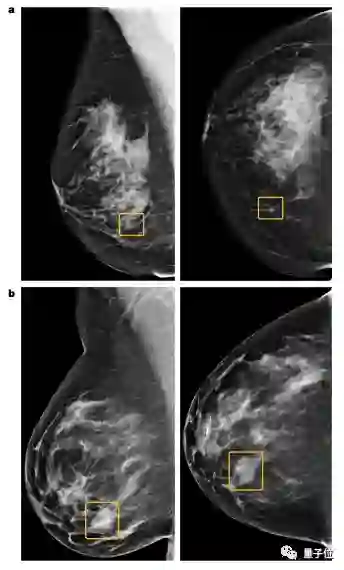

结果很有趣,虽然AI的诊断正确率高于人类,但是AI和人眼所遗漏的诊断却彼此互补。AI能捕捉到人类的遗漏,人类也能捕捉到AI的遗漏

a图中的小型的不规则钙化结构被AI识别出来,但是6位放射科医生都没有识别出来

b图中的大密度块状恶性肿瘤被6位放射科医生识别出来,但是AI却没有识别出来